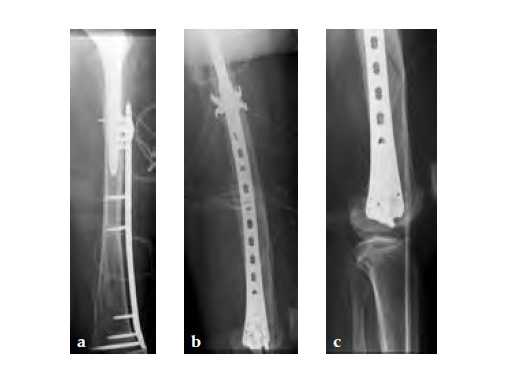

Case 1: A 78-year-old female sustained a periprosthetic fracture, Vancouver type C, 9 years after a total hip arthroplasty.